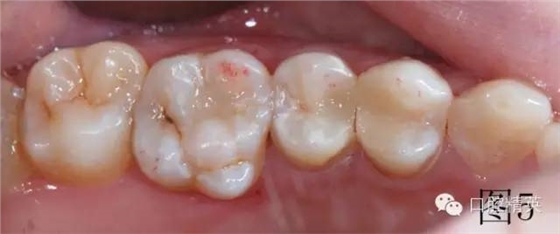

調(diào)牙合,圖5中上頜第一磨牙近中頰尖有紅色咬合點(diǎn),此為牙合干擾點(diǎn),調(diào)磨至沒有,最后拋光。治療結(jié)束,邊緣非常密合,患者非常滿意,沒有感到橡皮障任何不舒服的地方,唾液可自行吞咽。